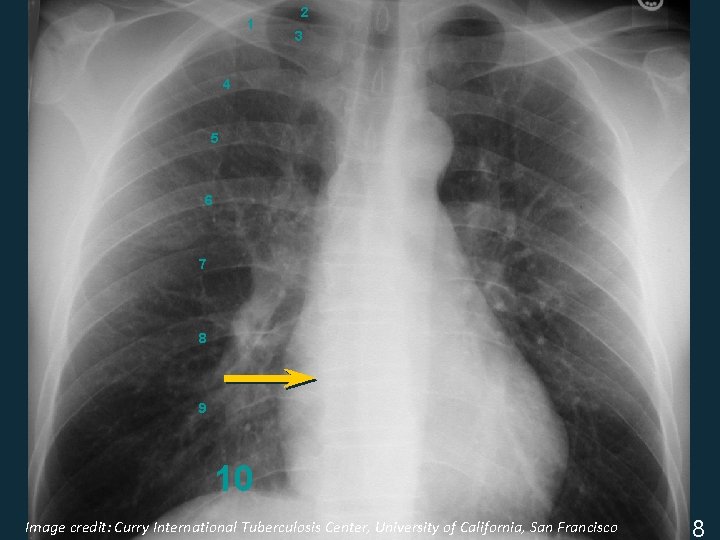

Assess CXR Technical Quality § Inspiratory effort • 9 -10 posterior ribs § Penetration • thoracic intervertebral disc space just visible § Positioning / rotation • medial clavicle heads equidistant from spinous process ISTC TB Training Modules 2009 7

Image credit: Curry International Tuberculosis Center, University of California, San Francisco ISTC TB Training Modules 2009 8

1 2 3 4 5 6 7 8 9 10 Image credit: Curry International Tuberculosis Center, University of California, San Francisco ISTC TB Training Modules 2009 8